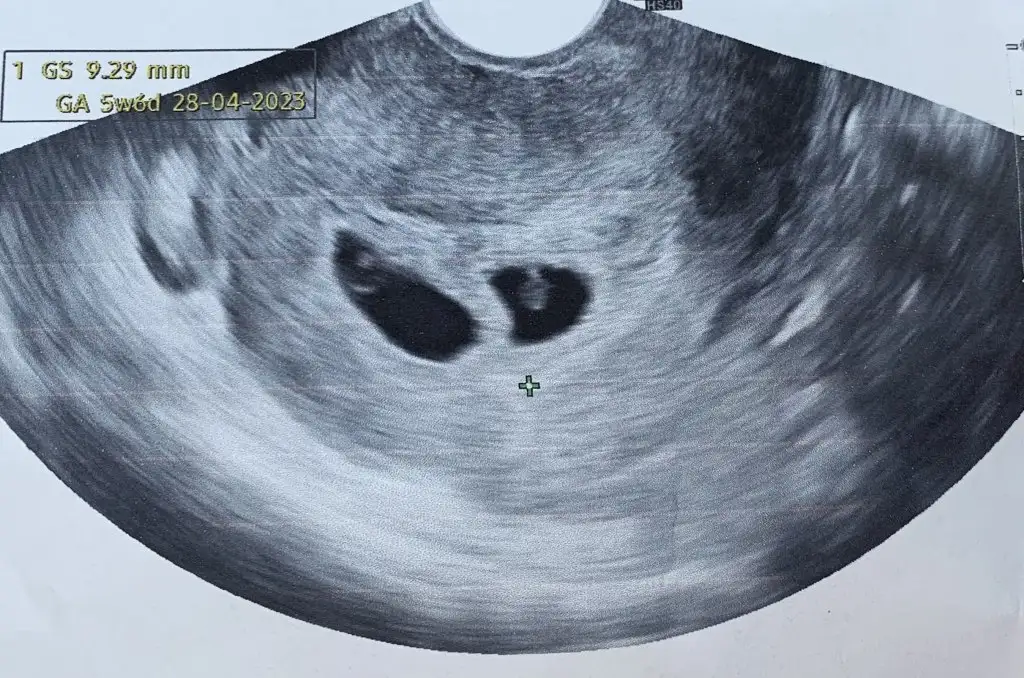

Yaaaa gözün aydın canımmm çok sevindimmmKızlar kesem gorundu cok sukur4+5 diye biliyordum 5+4mus 8cm kese olcumu mu oluyor Eki Görüntüle 3123385

Hayırlı olsun cnmmKızlar kesem gorundu cok sukur4+5 diye biliyordum 5+4mus 8cm kese olcumu mu oluyor Eki Görüntüle 3123385

Kesen 0.8 cm olmuşTeşekkürederimcanm.8 cm ne acaba

8 mm dır o herhalde dimiKesen 0.8 cm olmuş![]()